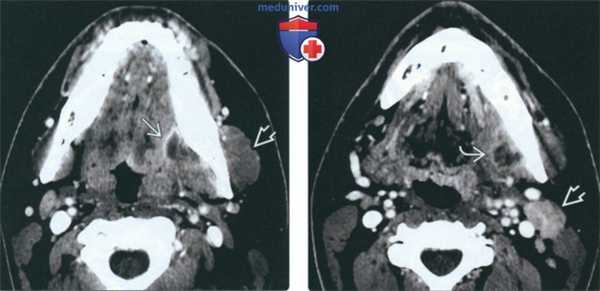

(Слева) На аксиальной КТ с КУ определяется большой многокамерный абсцесс внутреннего ЖП с вовлечением крыловидных мышц. Обратите внимание на утолщение и отек жевательной мышцы в наружном жевательном пространстве. У этого пациента 21 года девять месяцев назад был удален моляр слева, после чего появилась оталгия в сочетании с тризмом, неверно расцененные как проявления синдрома ВНЧС.

(Справа) На аксиальной КТ с КУ у этого же пациента определяется дальнейшее распространение абсцесса внутреннего ЖП в и отек жевательной мышцы.

(Слева) При КТ с КУ в аксиальной проекции определяется гигантский многокамерный абсцесс медиальных отделов жевательного пространства, распространяющийся на крыловидные мышцы. Обратите внимание на отек и припухлость жевательной мышцы в латеральном жевательном пространстве. Пациентка - девушка 21 года, которой девять месяцев назад был удален левый нижний моляр. Все это время она предъявляла жалобы на тризм и боль в ухе, которые врачи ошибочно принимали за заболевание височно-нижнечелюстного сустава.

(Справа) При КТ с КУ в аксиальной проекции у этой же пациентки видно, что абсцесс распространяется в нижележащие ткани. Также имеется отек жевательной мышцы.